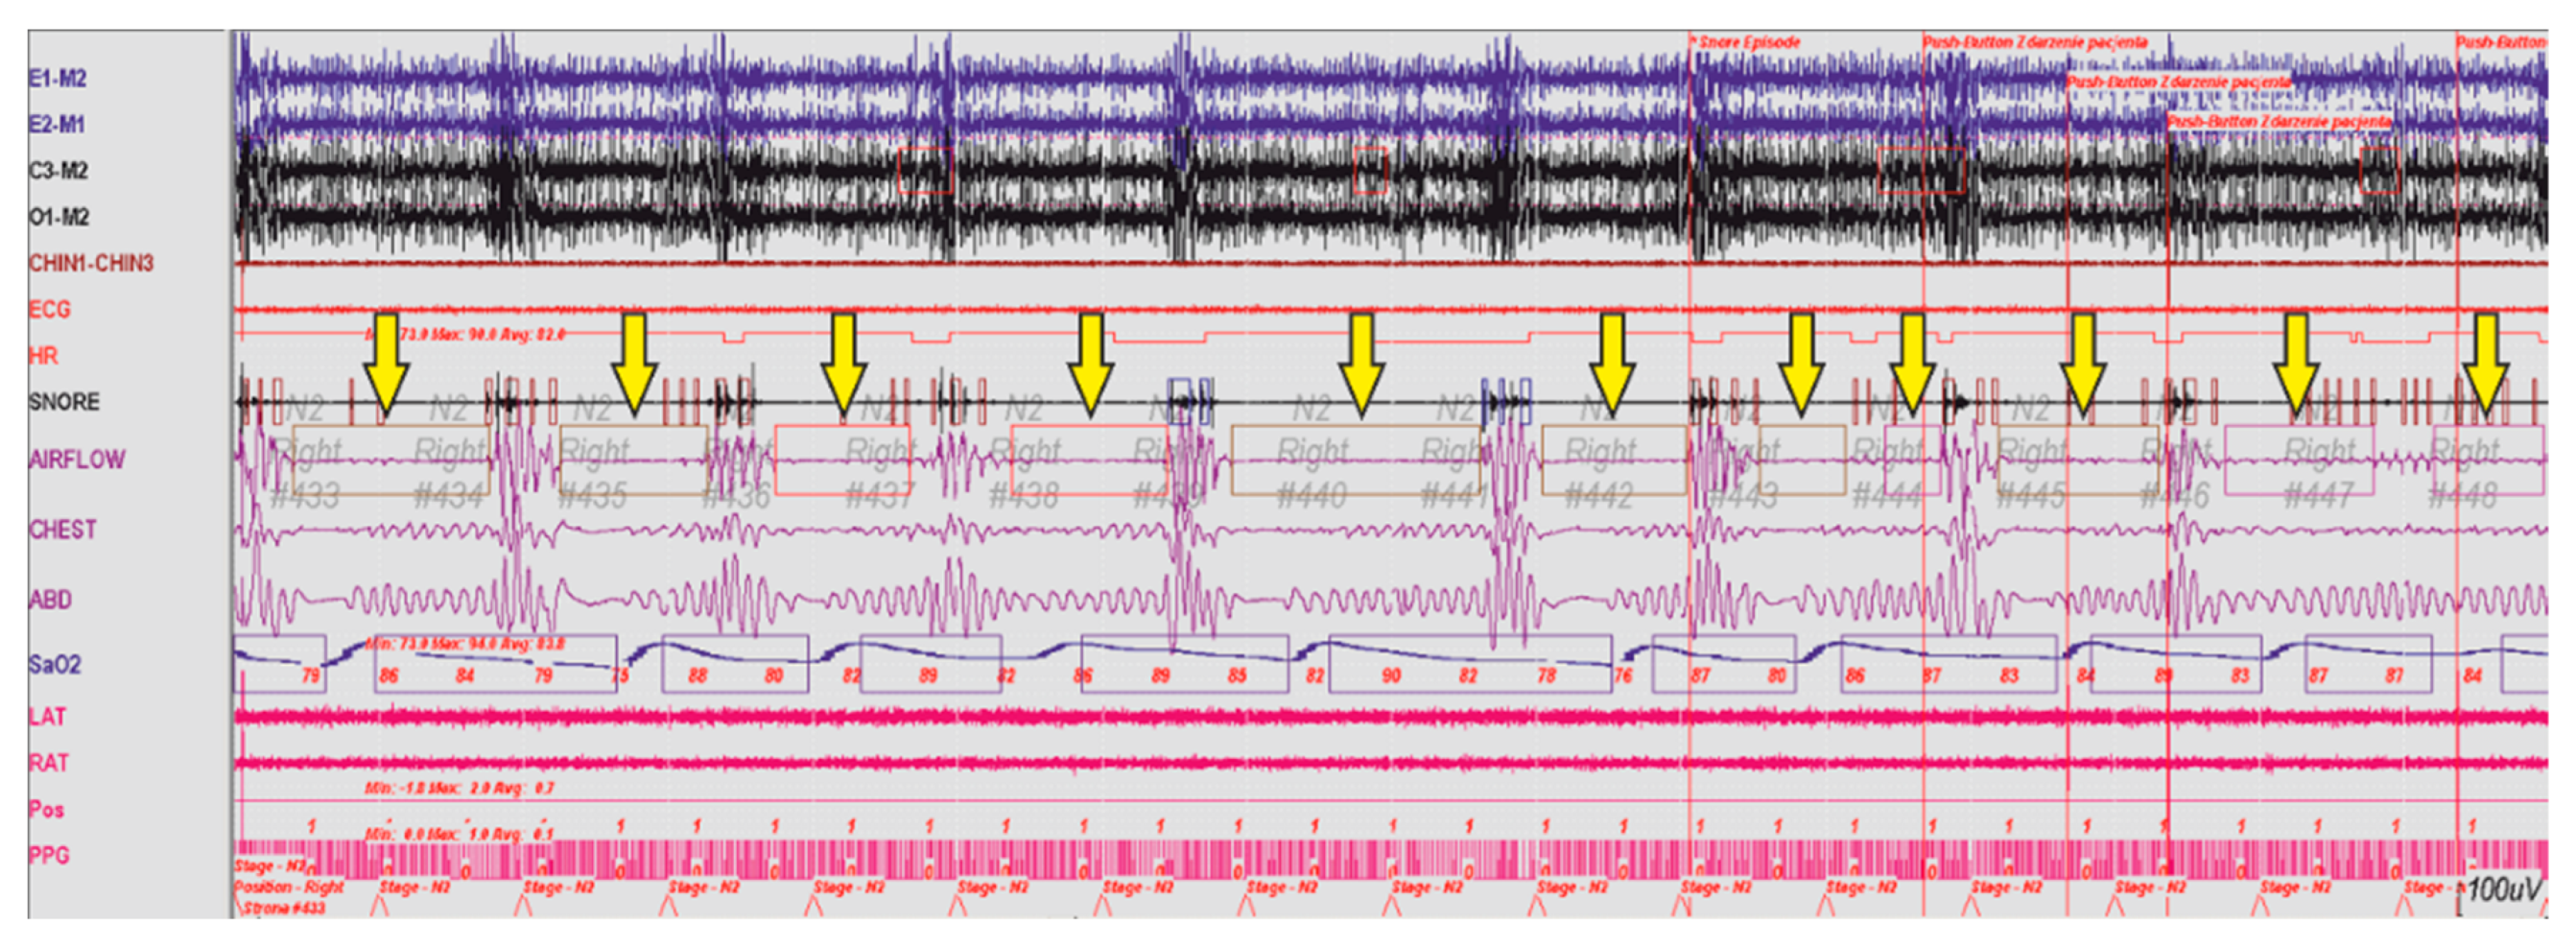

By detecting the risk of OSAS, we can indirectly prevent its development. Currently, the diagnostics of patients with sleep breathing disorders consists of conducting otolaryngologic or videoscopic examinations, as well as imaging studies (CT) and so on. A polysomnographic examination, colloquially also known as ‘sleep study’ consists of many procedures such as Electrocardiography (ECG), Electrooculography (EOG), Electroencephalography (EEG), Surface Electromyography (SEMG), Pulse Oximetry and oxygen saturation (SpO2). One of the elements of this study is monitoring patient’s respiratory activity. A fragment of a recorded polysomnographic examination is presented in Figure 15.

The information provided by the analysis of the presented case indicates the occurrence of numerous episodes of sleep apnea. As respiration stopped the blood oxygenation (SpO2) also decreased. The described device has a feature to continuously monitor the breathing action and to warn when such a situation occurs. Part of the recorded breath action can be seen in Figure 16, where two nostrils breathing were monitored. The apnea episode is marked with the red color, breath in and out, respectively, with blue and yellow.

Figure 15. Fragment of a polysomnographic examination of a patient with breathing disorders during sleep, the arrow marks episodes of apnea.